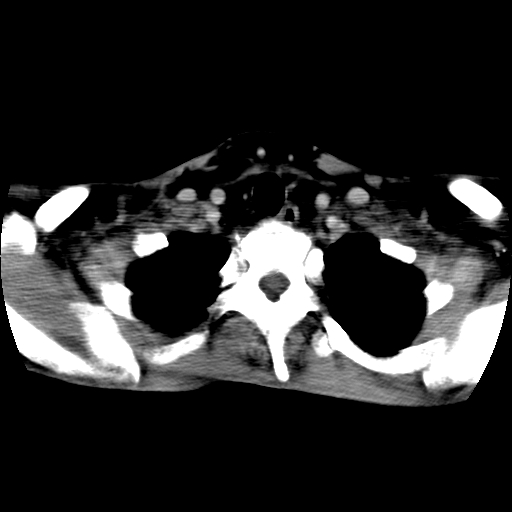

标题: CT24019:男,45岁,发现颈部肿物5个月。 [打印本页]

男,45岁,发现颈部肿物5个月,彩超示:双侧颈部及下颌部软组织增厚。

考虑双侧颈项部良性对称性脂肪增多症。

双侧颈项部脂肪沉积

双侧颈项部脂肪沉积。